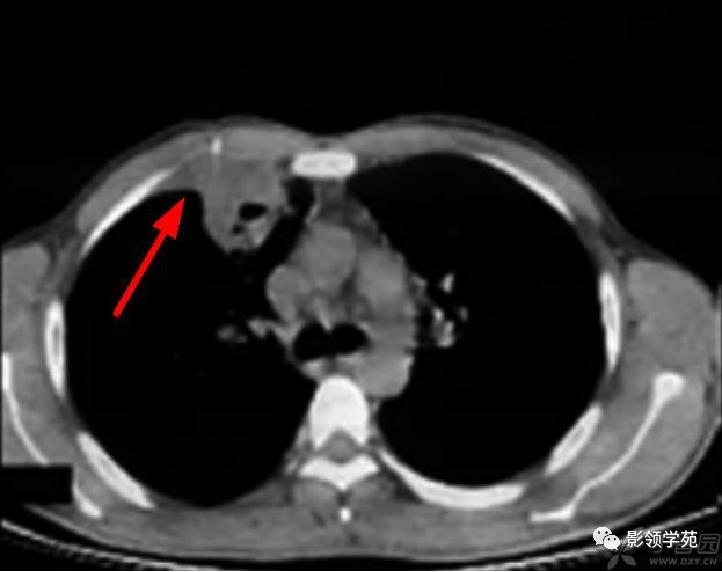

病例8:右上肺胸膜下病灶,伴厚壁空洞,邻近胸膜楔形增厚。

肺内多发结节和肿块是肺Wegener肉芽肿最常见的影像征象,表现为两肺散在分布、多发大小不等类圆形结节或肿块影,以两肺中下野分布多见。部分结节和肿块内可见空洞,洞壁多较厚,内缘光滑或不规则,空洞呈边缘性强化。合并感染时空洞内可形成液-气平面。结节或肿块周围一般都有较短毛刺,部分病灶有长毛刺与邻近的胸膜相连,表现为胸膜凹陷征。这与病理上结节周围存在大量成纤维细胞以及以纤维化形式愈合有关。

结节或肿块周围可见晕轮征、供养血管征。晕轮征提示肺结节或肿块出血,CT表现为结节或肿块周围磨玻璃密度影;供养血管征CT表现为血管影进入结节或肿块内,提示病变以血管为中心生长。